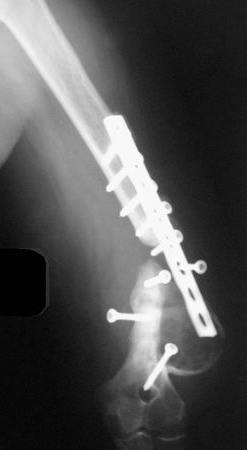

На примере два случая, извиняюсь за качество снимков, снимки и случаи из бывшего союза.

Первая больная с "успехом" была прооперирована 6 раз различными методами открытого и закрытого

остеосинтеза, включая то, что в Кисловодске заезжим австралийским "кудесником" на ложный сустав уложена скорлупа от страусиновых яиц. Последняя операция одиноким локинг плейт в одной из клиник.

Через год по поводу тех же проблем сделали ревизию, оригинальную пластину оставили как есть, только укрепили добавлением еще одной пластины и сделали костную пластику.

Через два месяца увидели признаки консолидации.

Второй случай, также после множественных операций:

пластина, аппарат, серкляж и парез нерва.

Также ревизия, из-за низкого состояния доступ был

сделан через остеотомию локтевого отростка.

Ложный сустав фиксирован двумя локинг плейт с

аутокостной пластикой, также через два месяца увидели признаки консолидации.

Движение в суставе разрешили в две недели.